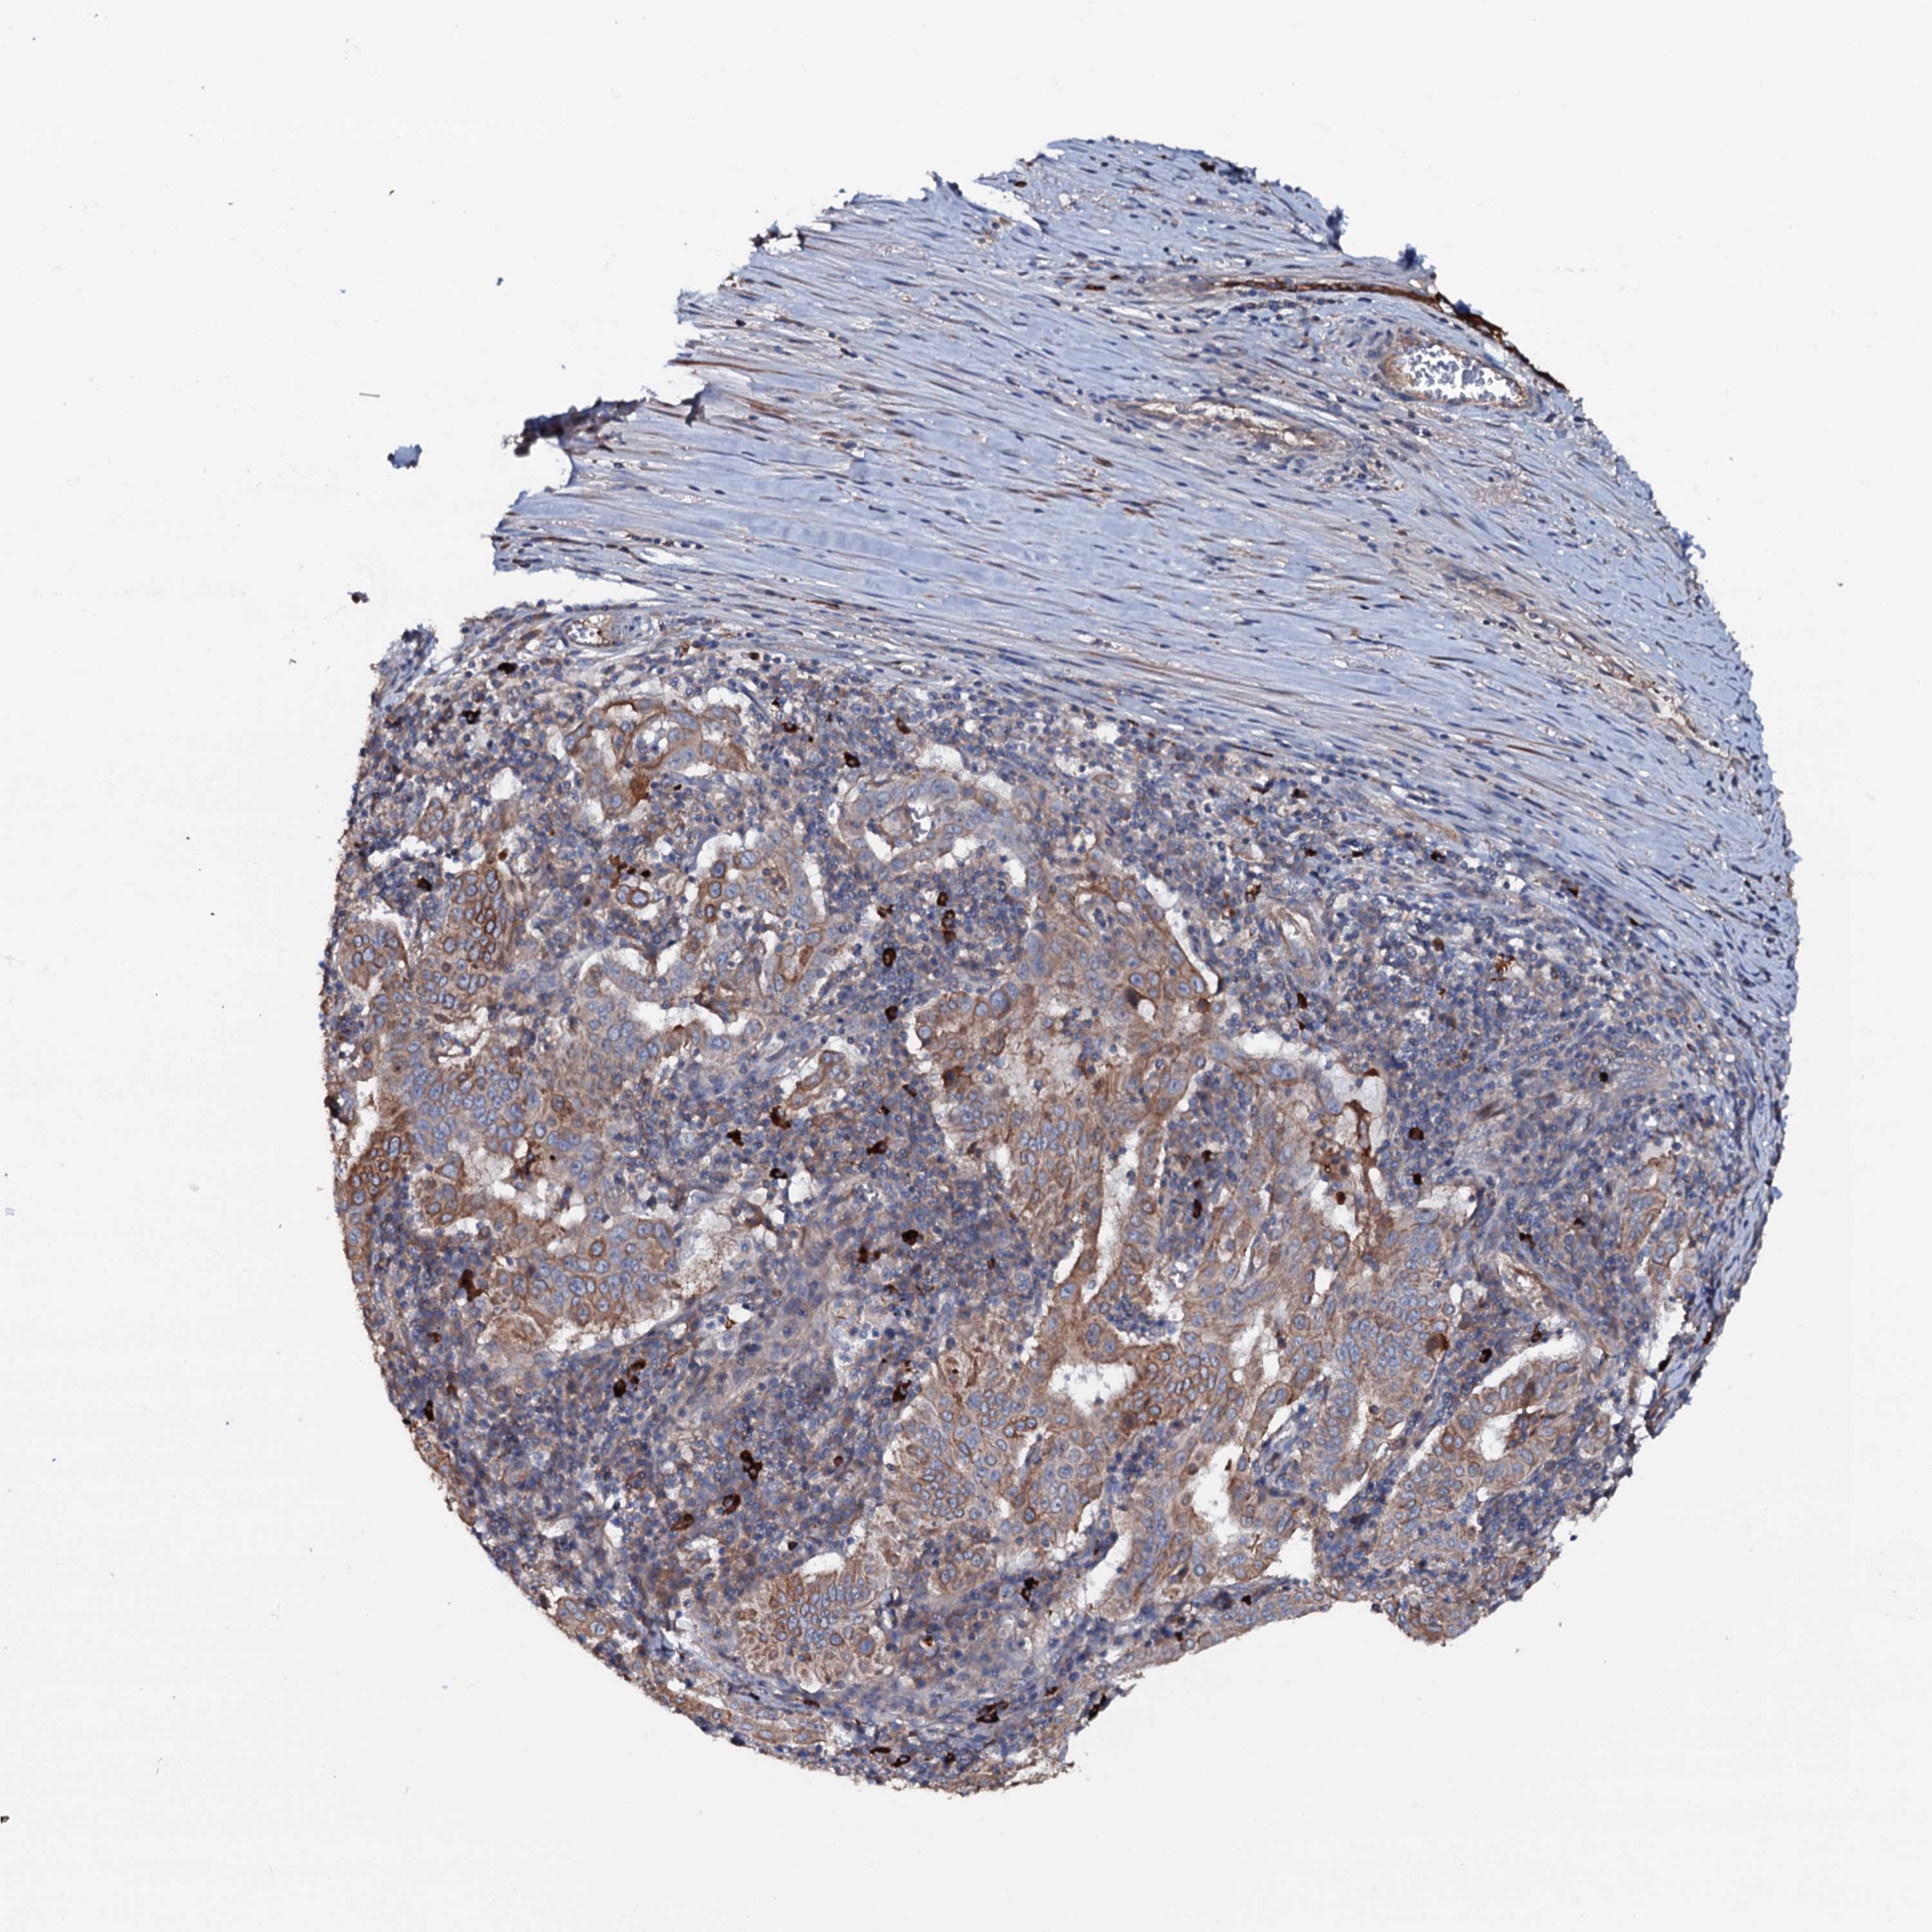

PANCREATIC CANCER - Protein expressioni

A mouse-over function shows sample information and annotation data. Click on an image to view it in a full screen mode. Samples can be filtered based on level of antibody staining by selecting one or several of the following categories: high, medium, low and not detected. The assay and annotation is described here.

Note that samples used for immunohistochemistry by the Human Protein Atlas do not correspond to samples in the TCGA dataset.

Antibody stainingi

Antibody staining in the annotated cell types in the current human tissue is reported as not detected, low, medium, or high, based on conventional immunohistochemistry profiling in selected tissues. This score is based on the combination of the staining intensity and fraction of stained cells.

Each image is clickable and will lead to virtual microscopy that enables deeper exploration of all samples and also displays staining intensity scores, fraction scores and subcellular localization as well as patient and tissue information for each sample.

Antibody HPA020873

Antibody HPA040413

Staining

High

Medium

Low

Not detected

Intensity

Strong

Moderate

Weak

Negative

Quantity

>75%

75%-25%

<25%

None

Location

Nuclear

Cytoplasmic/membranous

Cytoplasmic/membranous,nuclear

Adenocarcinoma, NOS